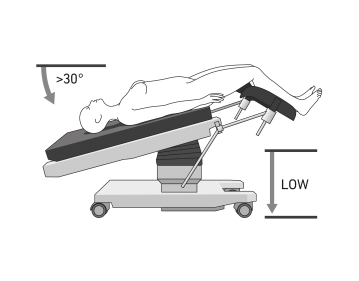

- O posicionamento é realizado na posição de litotomia (ou de forma mais segura em suportes de pernas retas separáveis), idealmente em um grande colchão a vácuo ou tapete antiderrapante

- Suportes de ombro bilateralmente para prevenir que o paciente escorregue na mesa cirúrgica

Nota: É importante considerar o risco de lesão ao paciente pelos instrumentos se o paciente escorregar. Com mesas acopladas no sistema Xi, mudanças de posição intraoperatórias são possíveis sem desacoplamento. Se a técnica "Table-Motion" não estiver disponível, o robô cirúrgico deve sempre ser desacoplado e removido da mesa cirúrgica antes de qualquer mudança de posição